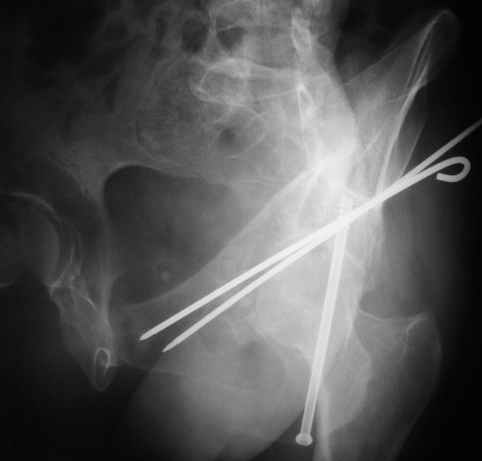

Однако есть альтернатива. Репозиция из подвздошного доступа тазовыми щипцами с разнодлинными браншами или тазовым пистолетом, а фиксация задней колонны через седалищный бугор или тазрвыми винтами 4,5 или каннюлированными 6,5 или 7,3. По-моему я посылал на ортофорум такой снимок, когда жаловался на ишемический неврит седалищного нерва через сутки после операции. Не забудь про шейку бедра - мне кажется будет хорош длинный PFN любой фирмы, какую ты найдешь, а нет так UFN + miss a nail, как это здорово делают мои земляки - Ебурбуки. Пока.

12.04.04